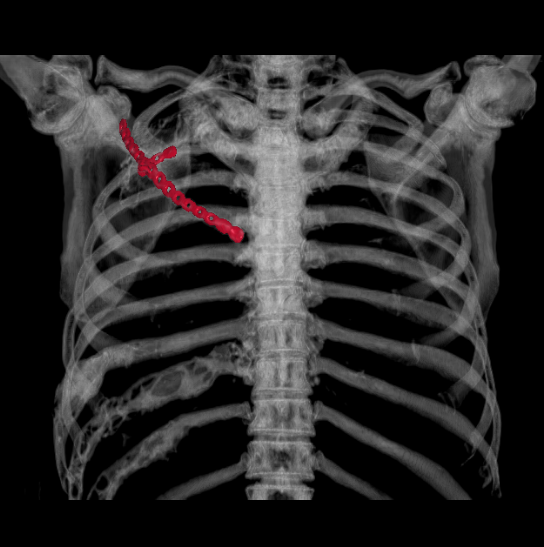

近日,重庆医科大学附属璧山医院(重庆市璧山区人民医院)胸心血管外科为患者实施全院首例胸壁肿物切除+胸壁重建术,成功为患者去除病灶,目前患者已康复出院。

荣腾浩副主任医师、杨富瑜主治医师经过全面检查,研究病例后认为:巨大肿物切除后,胸壁“软化”为常见并发症,进而导致反常呼吸,影响心肺功能,而患者为体力劳动者并且是家庭经济支柱,“重建”胸廓可使患者恢复劳动能力。胸心血管外科团队制定完善手术计划后,决定手术切除后予以Matrix -RIB板重建,手术过程顺利,术后无并发症,目前患者已康复出院。